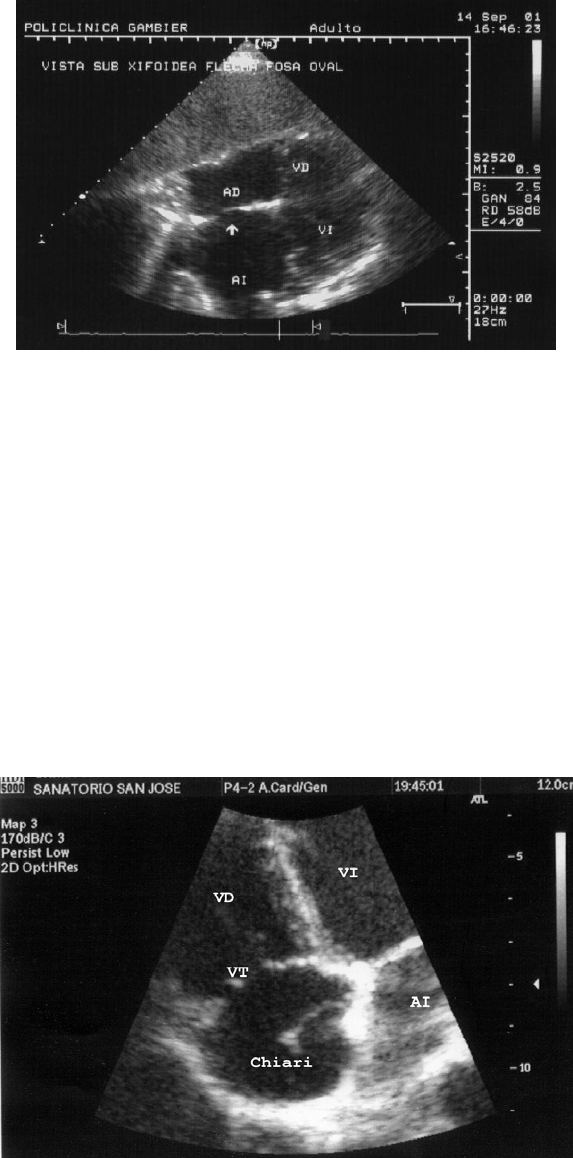

Fig: Vista sub xifoidea Esta ventana resulta útil para estudiar el pericardio y el

Septem inter auricular. AD: auricula derecha, VD: ventriculo derecho, AI:

auricula izquierda, VI: ventrículo izquierdo. Flecha señalando la fosa oval.

Una estructura anatómica que puede observarse desde esta ventana es la red

de Chiari (o válvula de la vena cava inferior) cuya trascendencia anátomo-

clínica fue estudiada con la configuración interna. Es una formación alargada

con movimientos serpenteantes que en la foto mide 22 x 9 mm y cuyo vértice

se dirige al septum interauricular.

Foto: vista apical con acercamiento en la auricula derecha. Se señala la valvula

tricuspide (VT), la auricula dercha (AD), y la red de Chiari que es una variación

anatómica de la valva de la vena cava inferior (caudal).